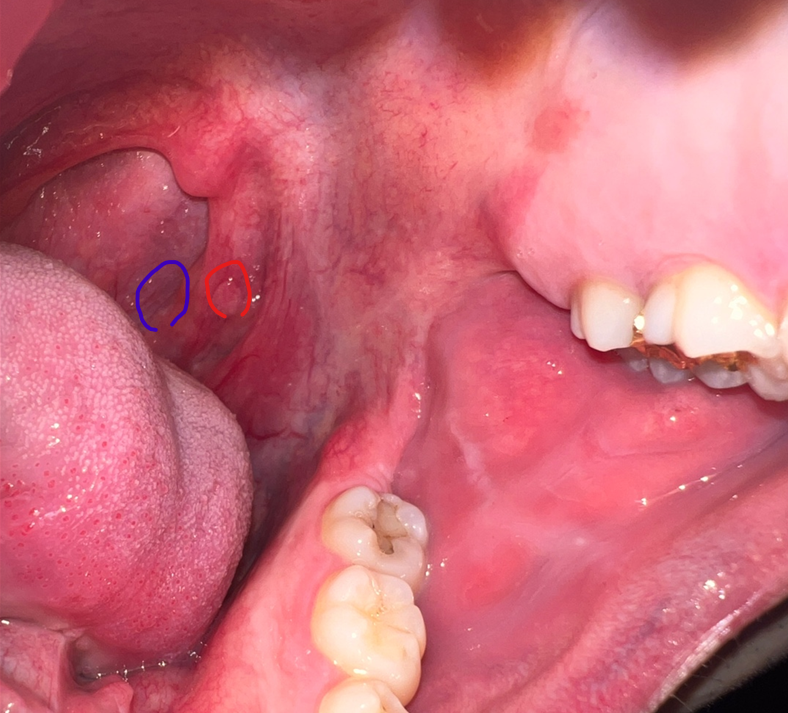

입안 편도쪽 혹? 덩어리같은게있는데요 말캉말캉하고 건드렸다 떼면 다시 돌아갑니다 (빨간원)

그리고 그 아래쪽에 뭐가 톡 나와있고 끝부분이 여드름처럼 하얗게 올라와있어요 (파란원)

안녕하세요. 이송재 의사입니다. 올려주신 사진으로는 작은 양성 혹으로 보입니다. 증상을 유발하지 않을 것이기 때문에 지켜보시기 바랍니다.